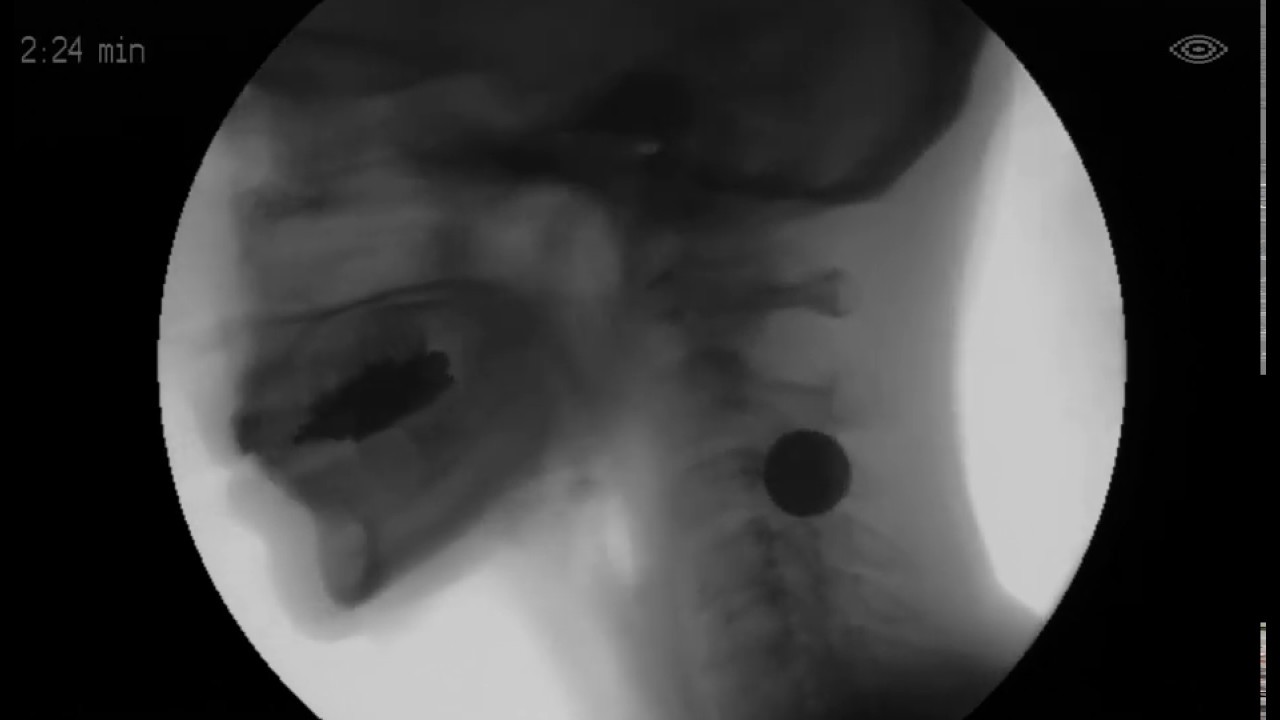

Barium Pill Embedded in Assure SlideZero (Phazix) YouTube Tablet Capsule Stuck In Throat a pill stuck in your throat can cause burning, difficulty swallowing, and breathing problems. learn what to do when a pill gets stuck in the throat, whether you are alone or with someone else. Learn how to prevent, treat, and handle a choking situation with water, food, or cpr. learn how to make it easier to swallow. Tablet Capsule Stuck In Throat.